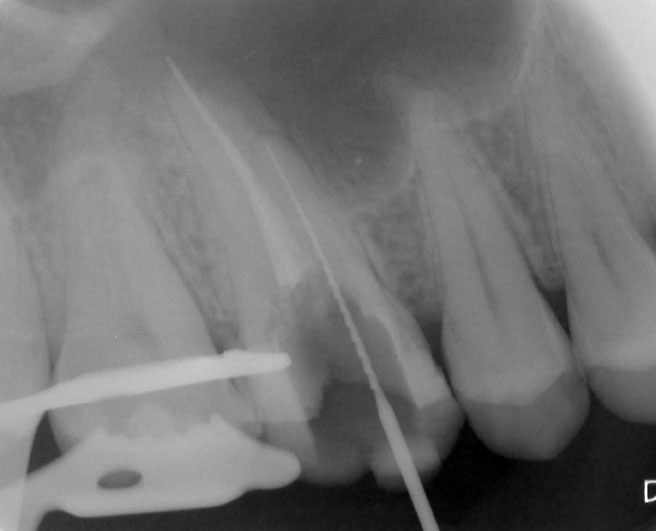

Patient N.M. wünscht eine Drittmeinung, zwischenzeitlich hatte er bereits einen zweiten Zahnarzt konsultiert. Dieser bestätigte eine insuffiziente Wurzelfüllung und vermutete eine Instrumentenfraktur im mb1 (Abb. 1).

Röntgenbefund

Mittels Röntgenaufnahme lässt sich ein frakturiertes Instrument in mb1 vermuten. Des Weiteren scheint es, als sei der distale Wurzelkanal sowie der mb2 nicht abgefüllt worden, was sich zu einem späteren Zeitpunkt der Behandlung bestätigen sollte. Der Patient wurde vom vorbehandelnden Zahnarzt über die Fraktur nicht aufgeklärt.